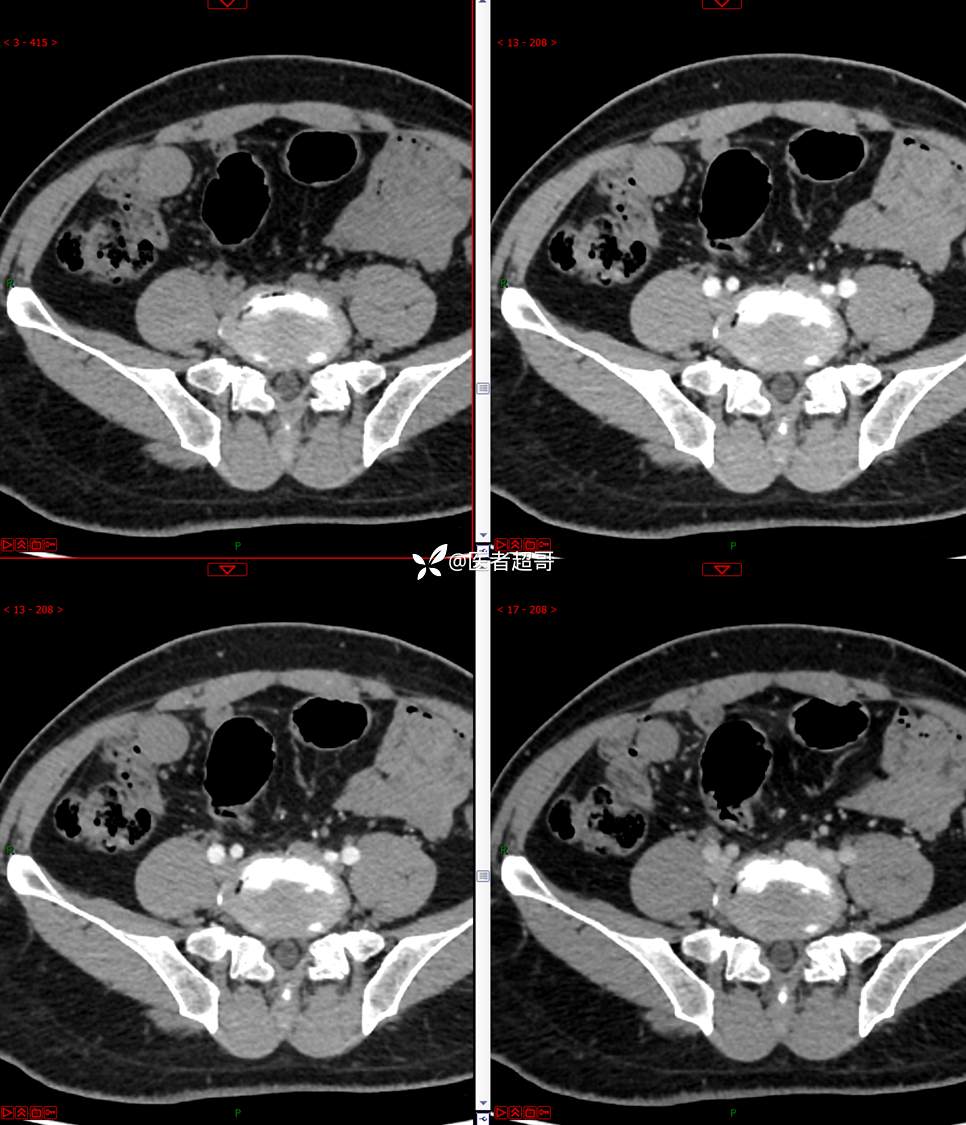

【影诊笔记747】结节不大,挺有意思的,做手术了,请赏析!

男,48岁 0200608 01

主诉:腹痛1月余。

现病史:患者1月余前无明显原因及诱因出现腹痛,脐周为著,为持续性隐痛,无发热,无恶心、呕吐,无腹泻,伴反酸,无胸闷、憋气,无呕血、黑便,至我院门诊就诊,查肝胆胰脾肾彩超诊断:肝胆胰脾双肾未见异常,下腹部实性团块,建议进一步检查,血淀粉酶46U/L,血常规未见明显异常,自服“肠炎宁”药物治疗,效果欠佳,现患者为行进一步治疗,门诊以“腹痛待查 腹腔肿物”收入院。患者自发病以来,神志清,精神可,饮食、睡眠可,大小便正常,体重较前无明显减轻。